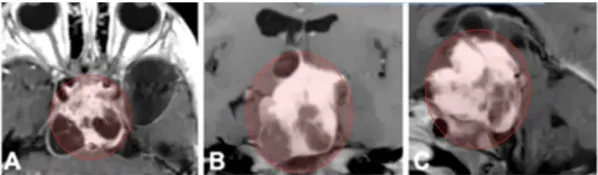

8岁男孩卢卡因视路-下丘脑胶质瘤引起视力受损而就诊,影像显示肿瘤为视路-下丘脑胶质瘤(OPHG),向上突入第三脑室并达室间孔(Monro孔)(A-C)。

巴教授选择经眶颧入路实现肿瘤全切。